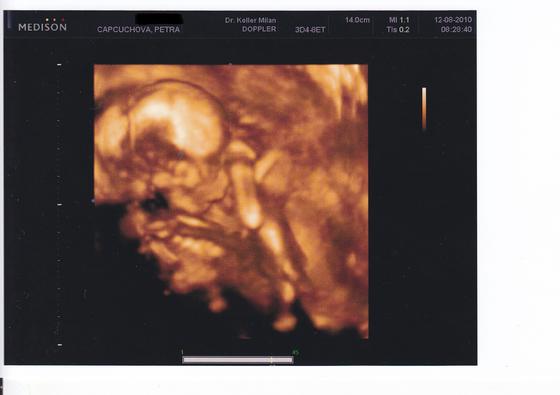

12.8.2010 (17+2) bylo provedeno další utz vyšetření a kontrola. Opět je vše vpořádku a fotečka se docela povedla. Byl se mnou u utz i přítel a byl natěšený, že konečně uviděl mimíska naživo. Poslechl si srdíčko a celého si ho prohlédl, akorát ještě pohlaví nám je pořád utajováno! S velkou radostí a potěšením jsme si odnesli fotečku ve 3D. Mímoš je 14 cm velký!